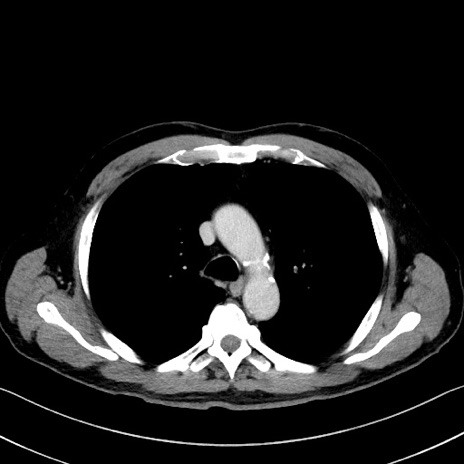

症例35(横断像)

【症例】70歳代 男性

【主訴】腹部膨満、嘔吐

【現病歴】昨日より腹部膨満感出現。本日増悪し、仙痛出現。嘔吐あり、受診。

【既往歴】糖尿病、胆摘後

【身体所見】BP 149/80mmHg、HR 74/min、BT 35.9℃、腹部:膨満、軟、圧痛なし。腸雑音減弱あり。上腹部正中切開瘢痕あり。

【データ】WBC 13500、CRP 1.72